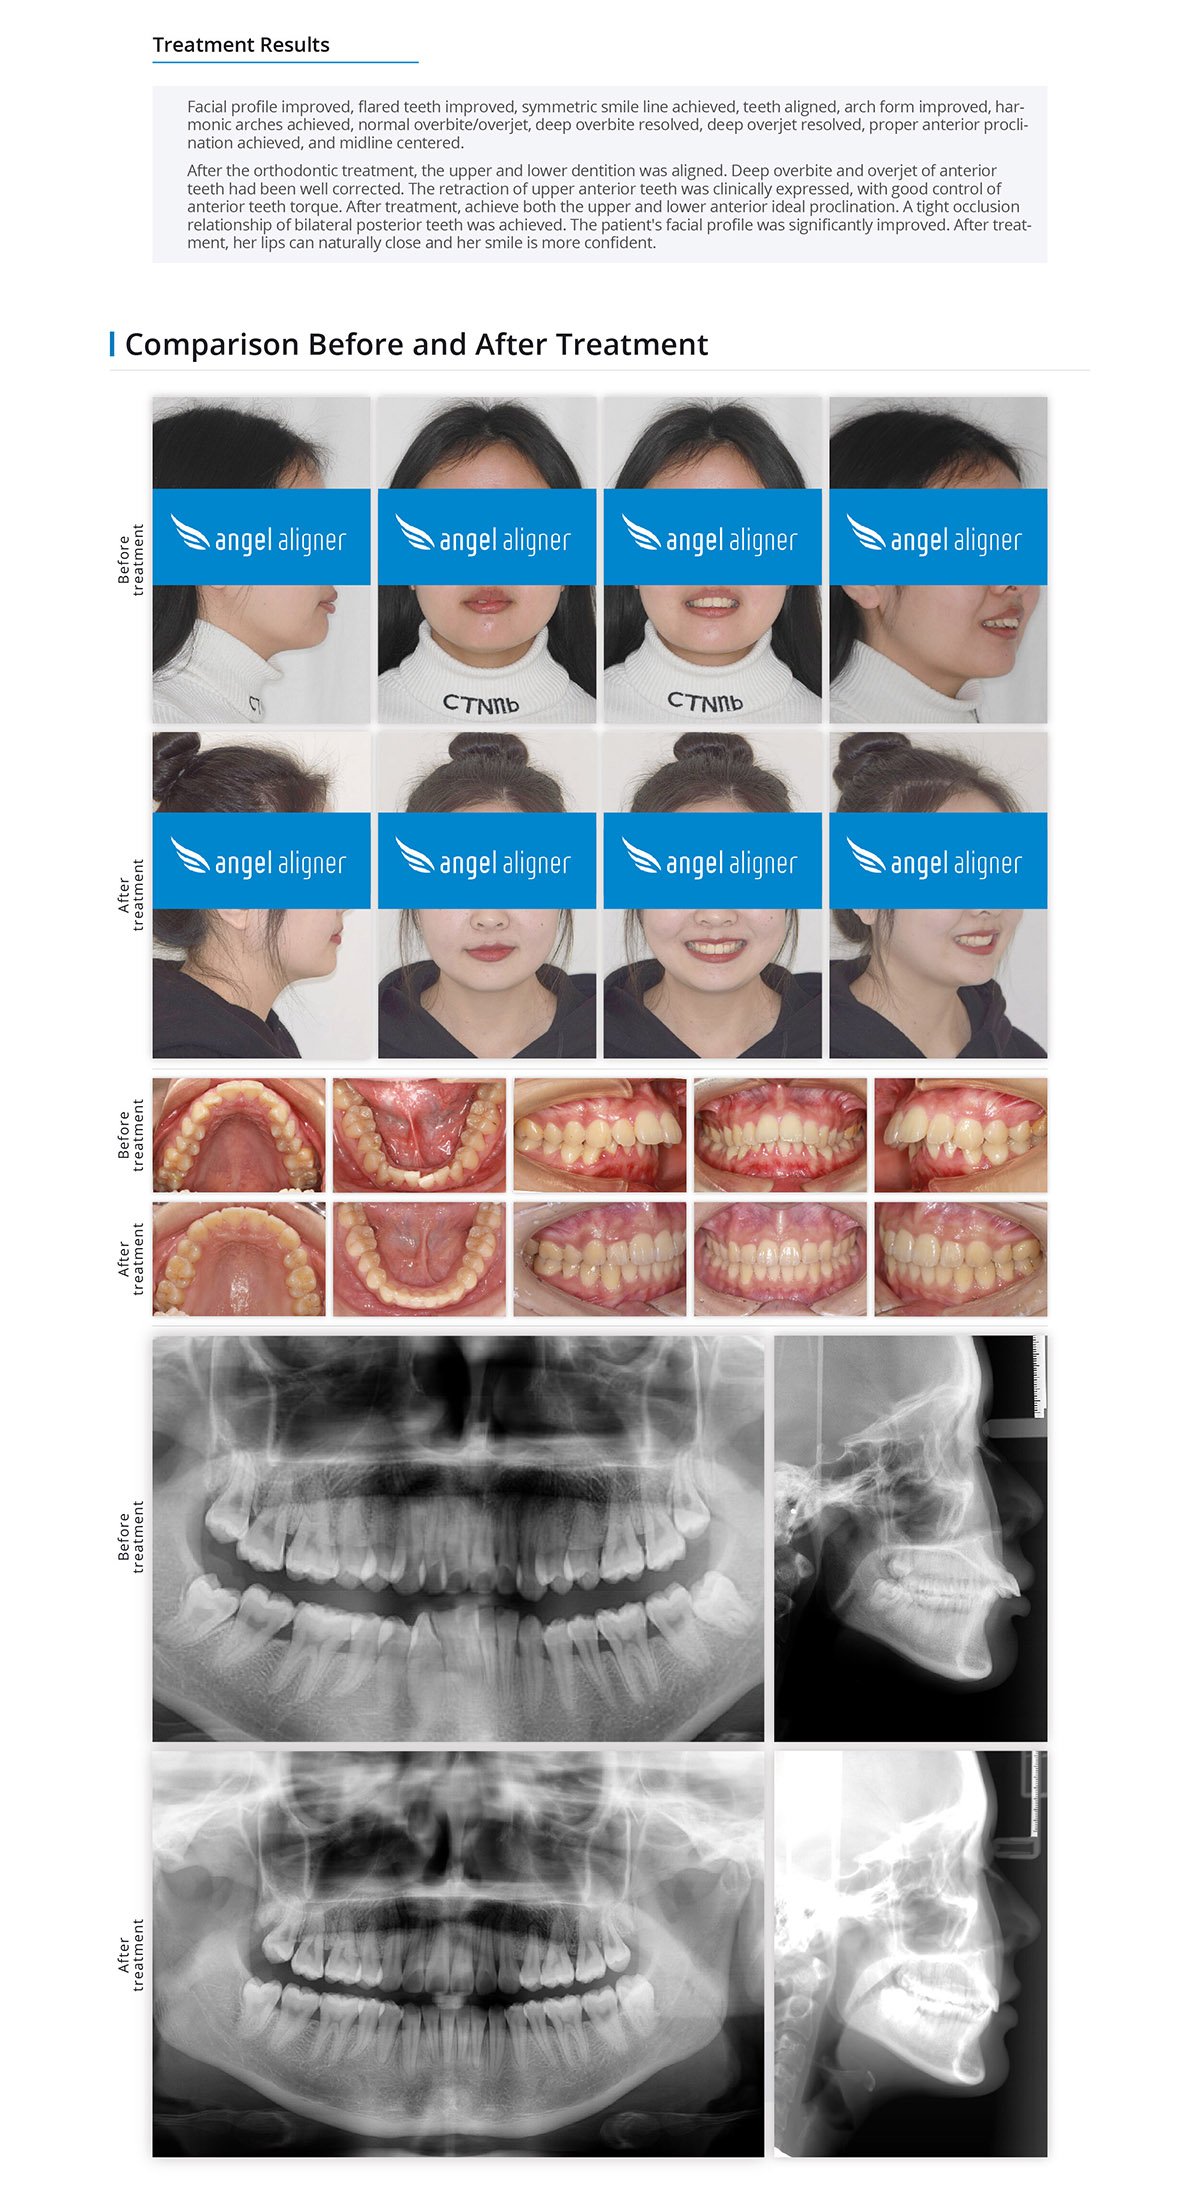

06

Secondary Orthodontic Treatment, Unilateral Tooth Extraction, And High Angle, Midline Deviation

Female, 26 years old

Permanent dentition

Angel Aligner Pro

Total treatment time: 33 months